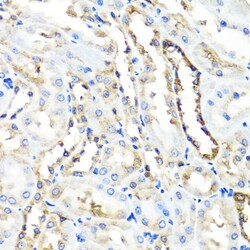

Immunogen sequence: RWAFNWDTKD IYRQRSRALV QAQHPDWPAP QVEAVAQDQF QGAARAWMAG TLQLGRALRP RGLWGFYGFP DCYNYDFLSP NYTGQCPSGI RAQNDQLGWL WGQSRALYPS IYMPAVLEGT GKSQMYVQHR VAEAFRVAVA AGDPNLPVLP YVQIFYDTTN HFLPLDELEH SLGESAAQGA AGVVLWVSWE NTRTKESCQA IKEYMDTTLG PFILNVTSGA LLCSQALCSG HGRCVRRTSH PKALLLLNPA SFSIQLTPGG GPLSLRGALS LEDQAQMAVE FKCRCYPGWQ APWCERKSMW; Positive Samples: Mouse liver, Mouse lung; Cellular Location: Lysosome.

This gene encodes a lysosomal hyaluronidase. Hyaluronidases intracellularly degrade hyaluronan, one of the major glycosaminoglycans of the extracellular matrix. Hyaluronan is thought to be involved in cell proliferation, migration and differentiation. This enzyme is active at an acidic pH and is the major hyaluronidase in plasma. Mutations in this gene are associated with mucopolysaccharidosis type IX, or hyaluronidase deficiency. The gene is one of several related genes in a region of chromosome 3p21.3 associated with tumor suppression. Multiple transcript variants encoding different isoforms have been found for this gene.

| ELISA, Immunohistochemistry (Paraffin), Western Blot, Immunocytochemistry | |

| Recombinant fusion protein containing a sequence corresponding to amino acids 136-435 of human HYAL1 (NP_1493492). | |